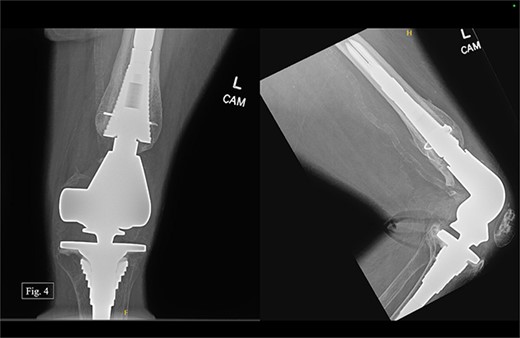

During her most recent visit in February 2024, roughly 4 years after DFR, the patient reported a pain score of 5/10 pain at rest, and bilateral AP, right & left lateral, right & left AP, and full leg-length X-rays were taken. Looking at the APand lateral imaging of the left knee, there were findings of DFR without signs of lucency or subsidence, and the hardware-maintained alignment was intact (Fig. 4). She was able to ambulate with moderate, 6/10 pain and had full passive ROM with similar pain. She was instructed to continue at-home physical therapy and non-steroidal anti-inflammatory drugs (NSAIDs) as needed for pain and to return to the clinic in 6 months for further evaluation.